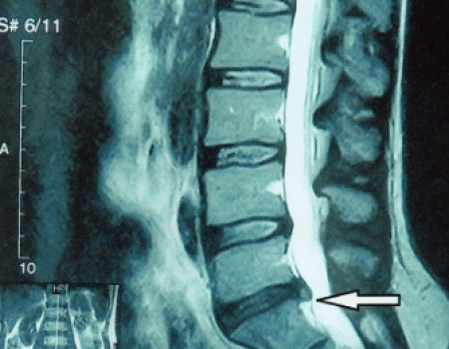

Tā kā pašus diskus var redzēt tikai, izmantojot CT vai MRI, ir indicēta magnētiskā rezonanse un rentgena datortomogrāfija, lai noskaidrotu skrimšļa iekšējo struktūru un veidojumus, piemēram, izvirzījumus un trūces. Tādējādi ar šo metožu palīdzību tiek precīzi noteikta diagnoze, un tomogrāfijas rezultāts ir indikācija un pat aktuāls ceļvedis trūces ķirurģiskai ārstēšanai neiroķirurģijas nodaļā.

- ja jums ir trūce, tā ir dinamiski jāuzrauga, regulāri jāveic MRI, jāizvairās no tā izmēra palielināšanas vai jāveic mūsdienīga minimāli invazīva ķirurģiska ārstēšana, jo bez izņēmuma visas konservatīvās osteohondrozes paasinājuma ārstēšanas metodes atstāj trūci vietā un novērš tikai īslaicīgus simptomus: iekaisumu, sāpes, šaušanu un muskuļu spazmas.